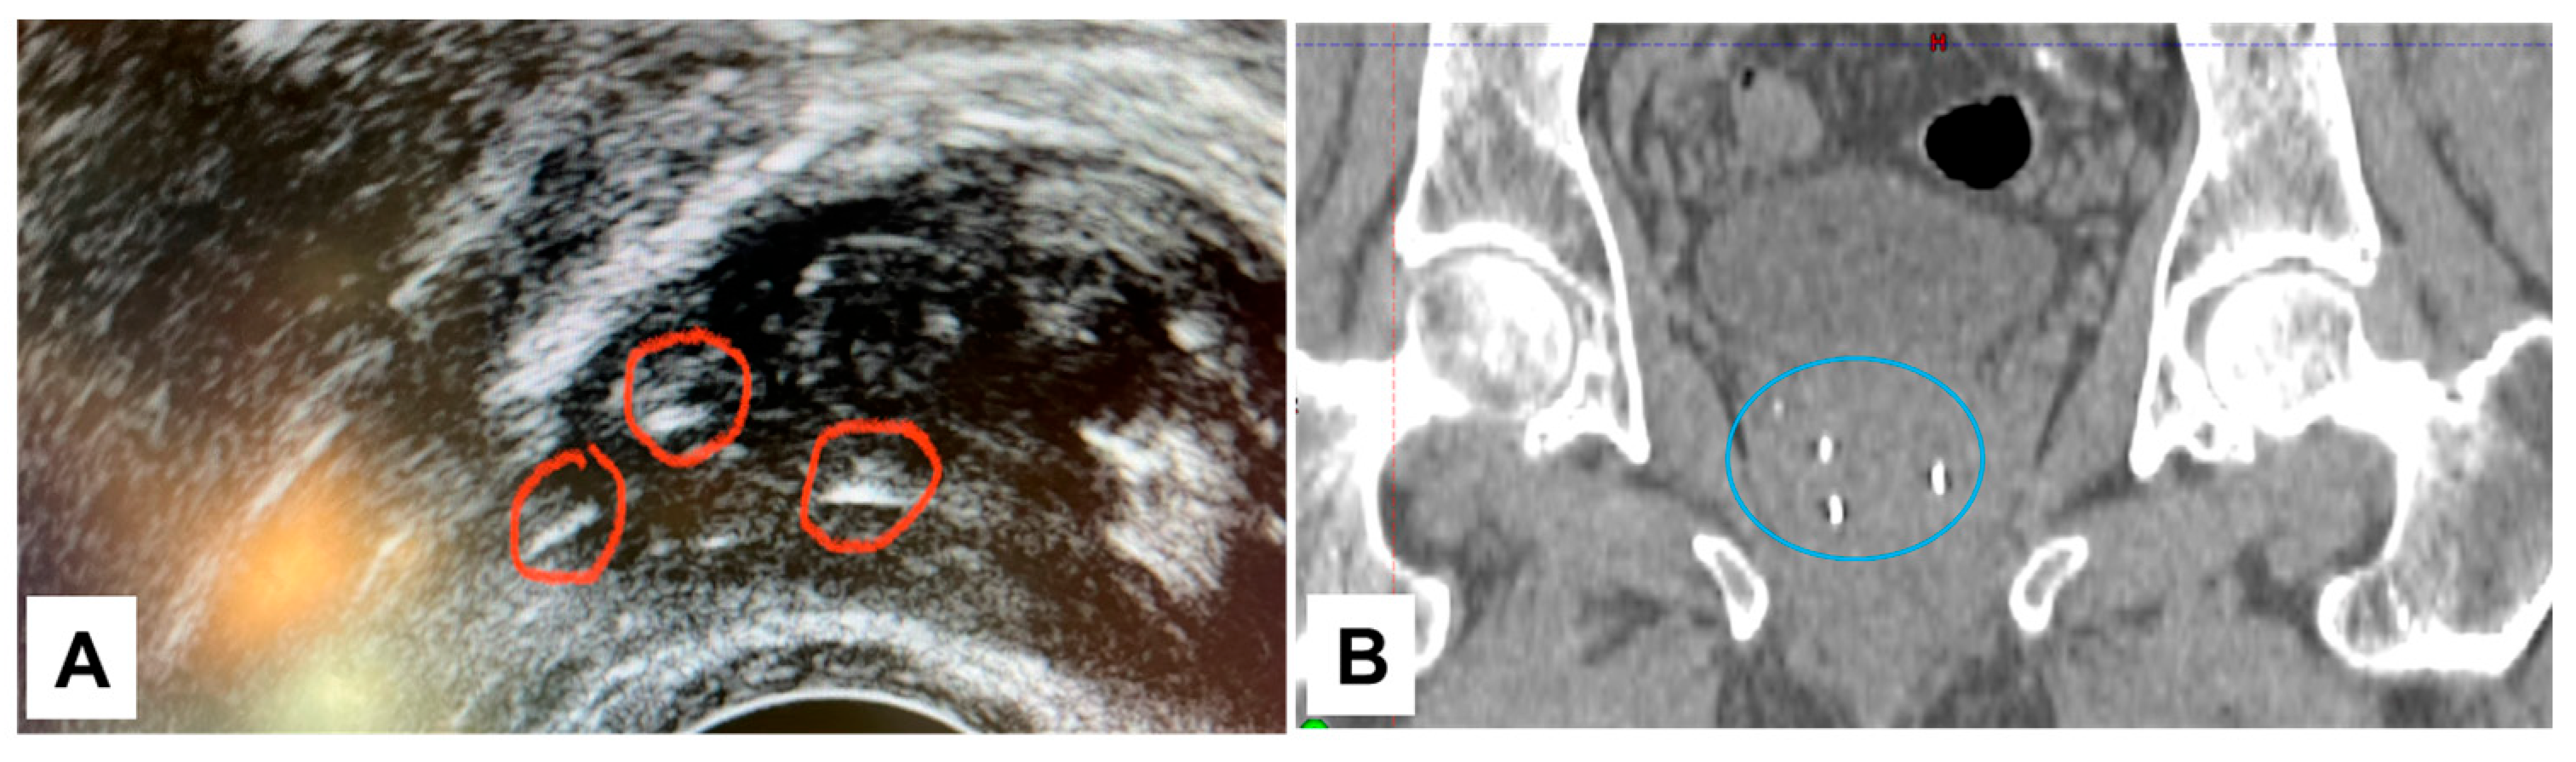

3.1. NOVA Marker Visibility in Phantom

3.4. Visibility of NOVA Markers in a Clinical Case